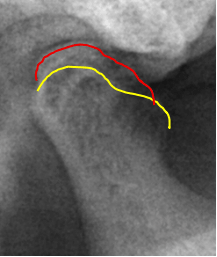

当院では、体の歪みを調べ、その方にとって無理のない安定した顎位を見つけ出し、その位置で噛み合わせを構築することを重要視した矯正治療を行っています。